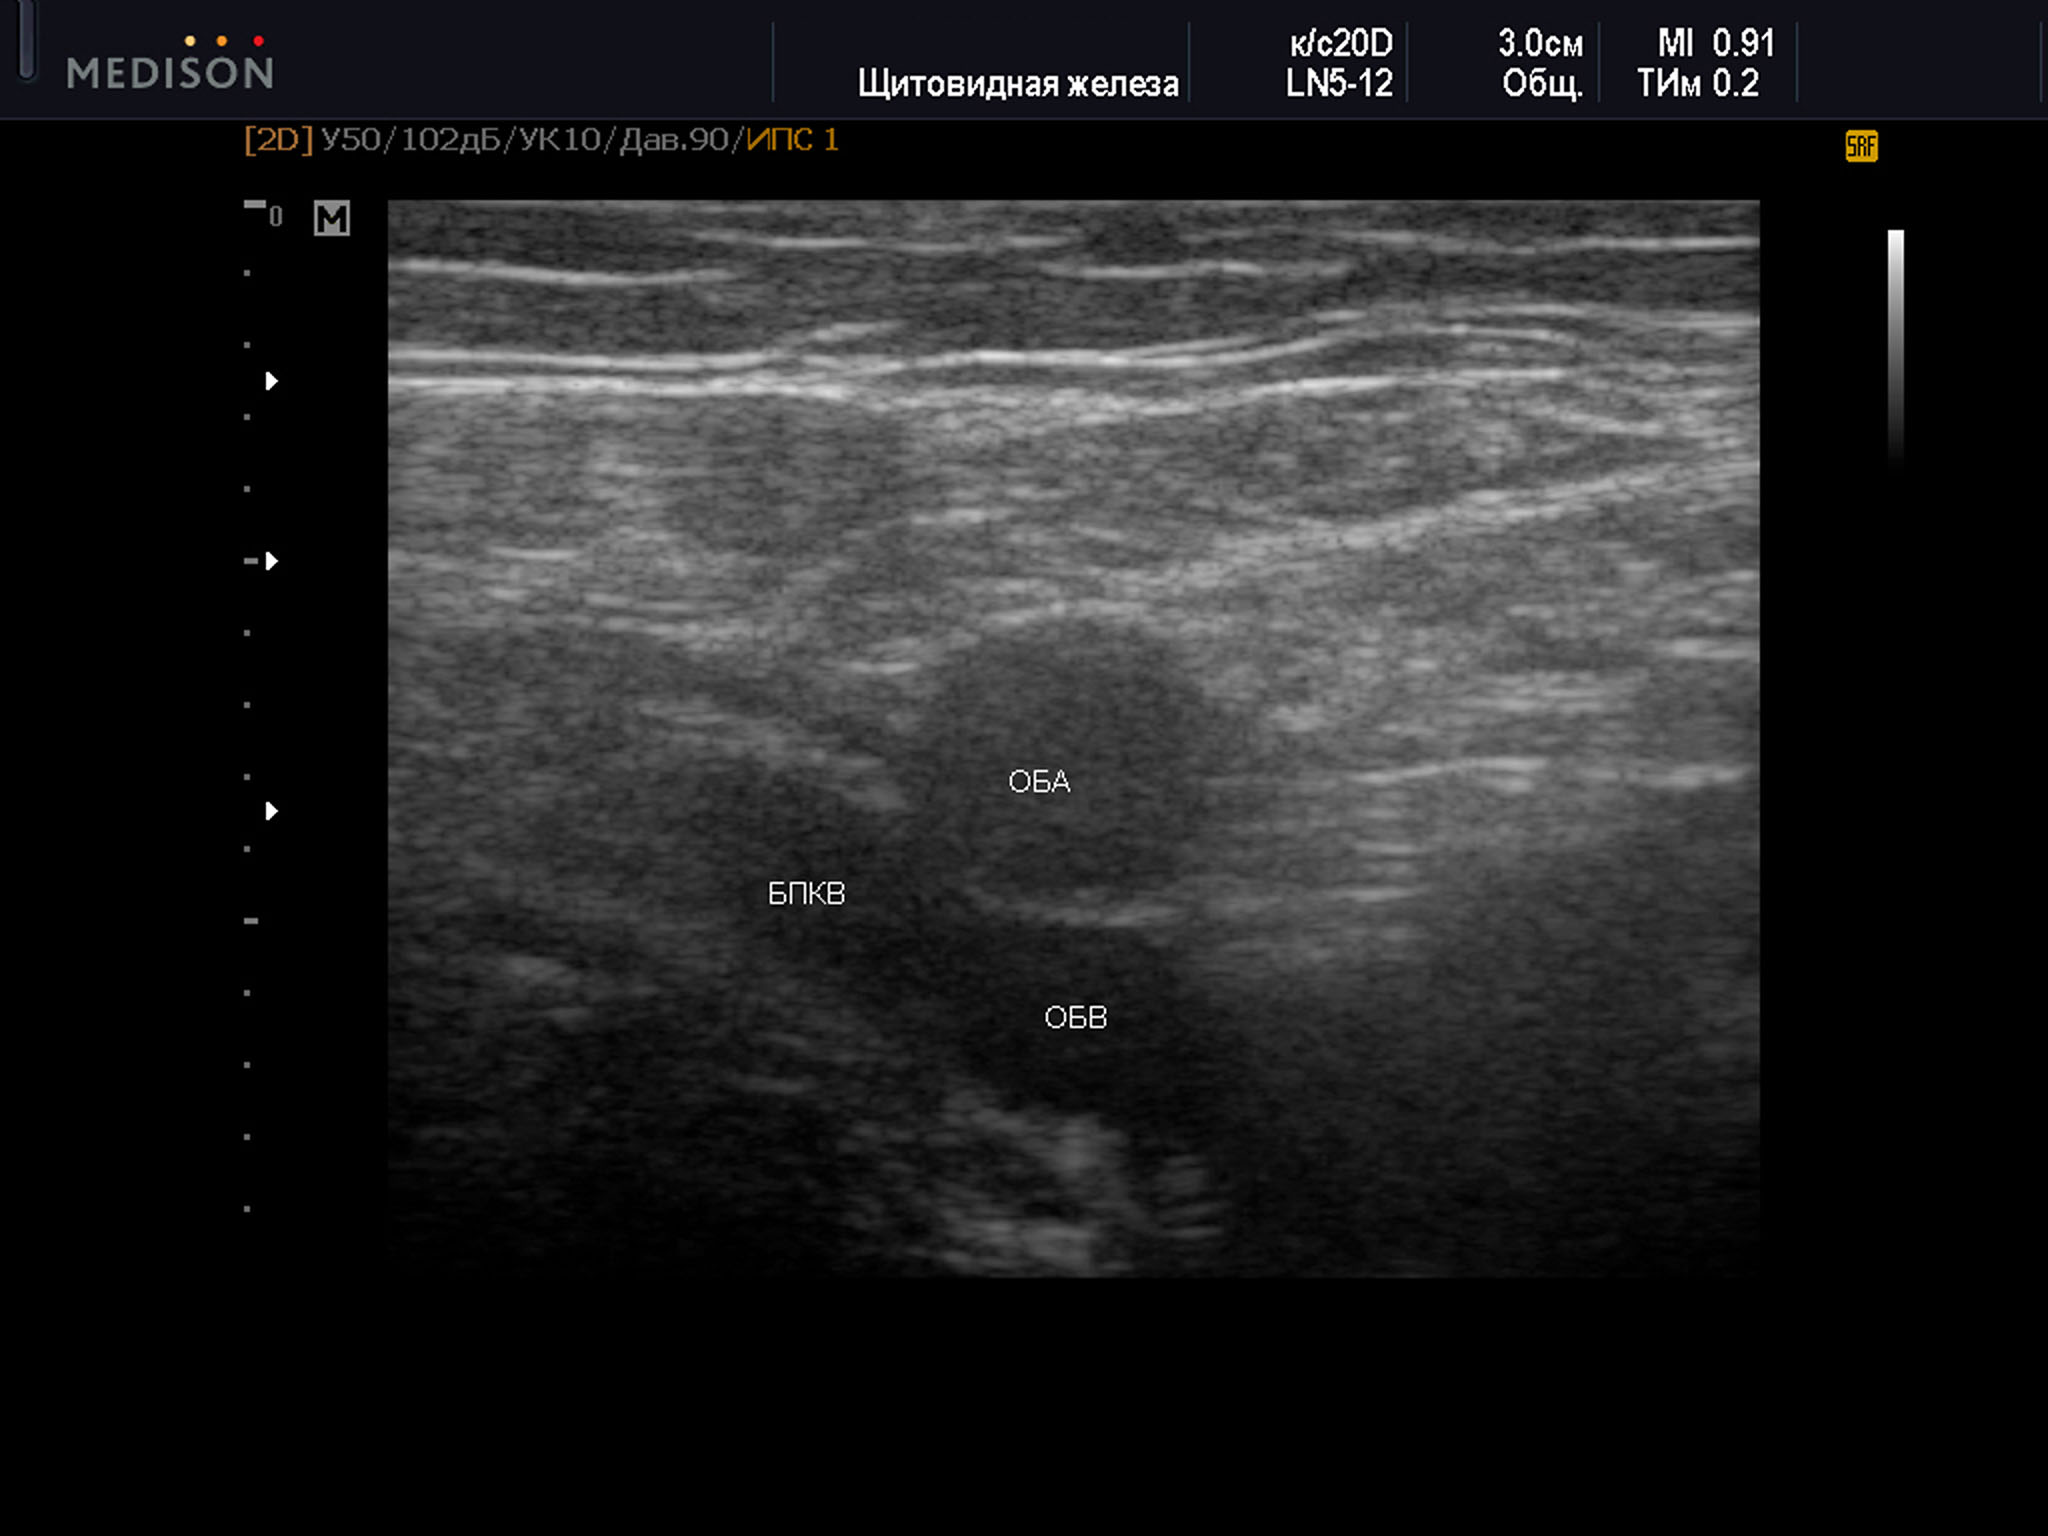

1 тип характеризовался полным прикрытием ствола бедренной веной за счет артерии (рис. 1):

Пример диагностического ультразвукового изображения на уровне верхней трети бедра, поперечное сечение общей бедренной вены и общей бедренной артерии, Тип 1 взаимного положения сосудов

SonoAce R7, линейный датчик, женщина, 69 лет.

ОБА – общая бедренная артерия; ОБВ – общая бедренная вена; БПКВ – большая подкожная вена бедра